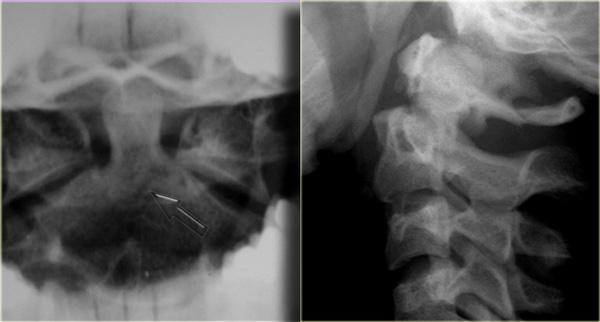

Hình bên trái minh họa loại gãy mỏm răng phổ biến nhất, đó là loại II với đường gãy qua nền mỏm răng.

Gãy loại II có xu hướng không liền xương (nonunion), xảy ra trong 64% trường hợp.